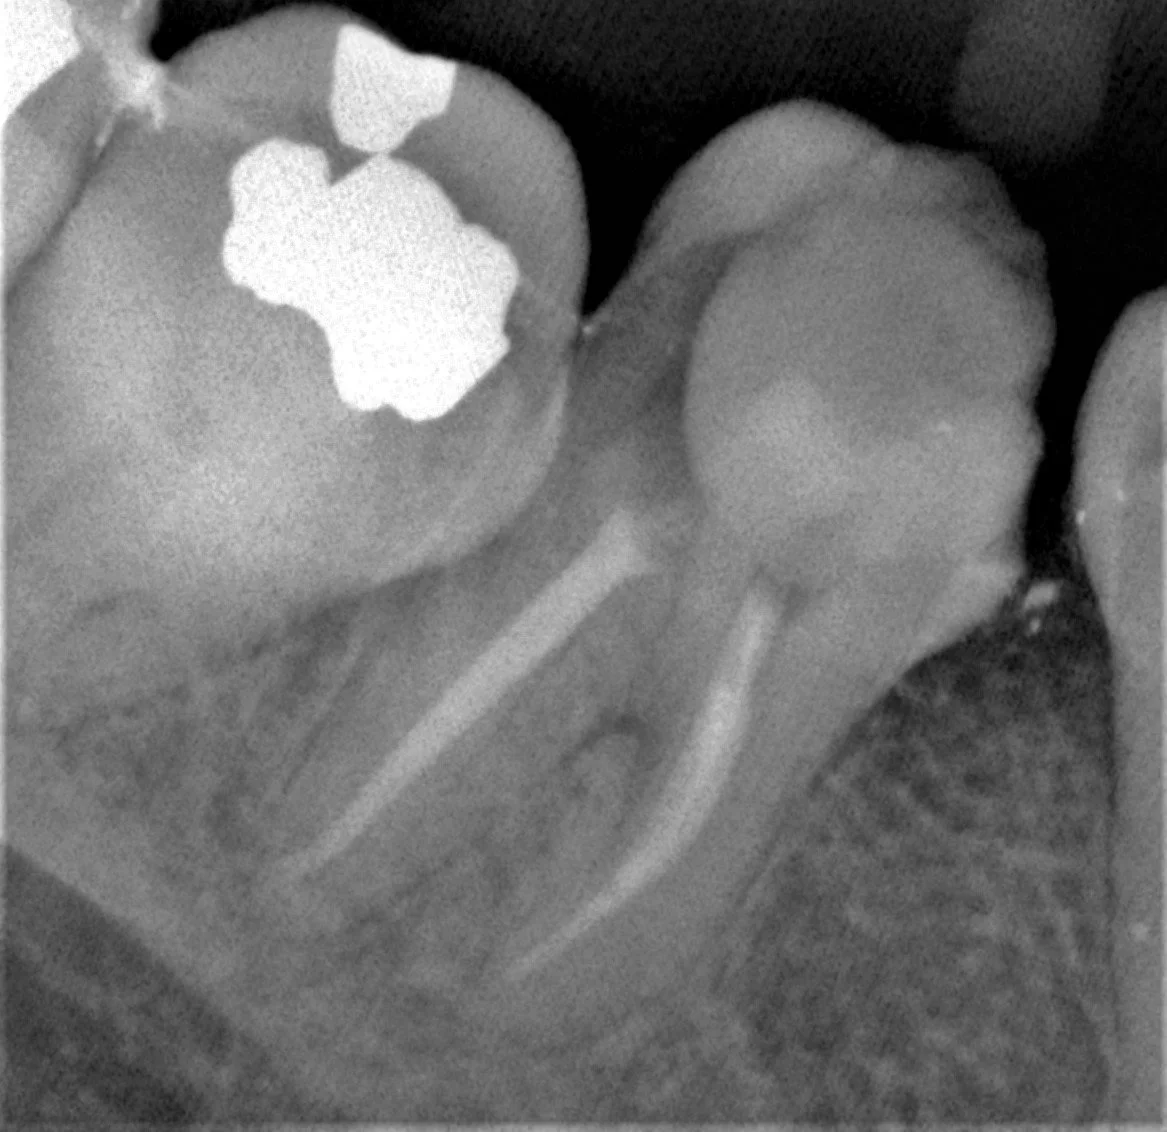

The first step in root canal therapy is establishing the right diagnosis and deciding whether the tooth can be saved - this means having a frank conversation with the patient and exposing an x-ray. This x-ray reveals a LARGE, INTIMIDATING cavity (middle tooth) that most dentists would elect to extract. However, the patient was very motivated to save his tooth and did not want it extracted. Luckily for the patient, Dr. Brian Vu is even more motivated than him. Let’s see what the tooth looks like in real life.

The x-ray looks fantastic with all disinfection and sealing materials completely making its way to the end of the root. The tooth has 3 roots and 4 canals (if you look carefully, 1 canal joins another canal). That’s a lot of work, but we aren’t done yet. It’s time to put the tooth back together.